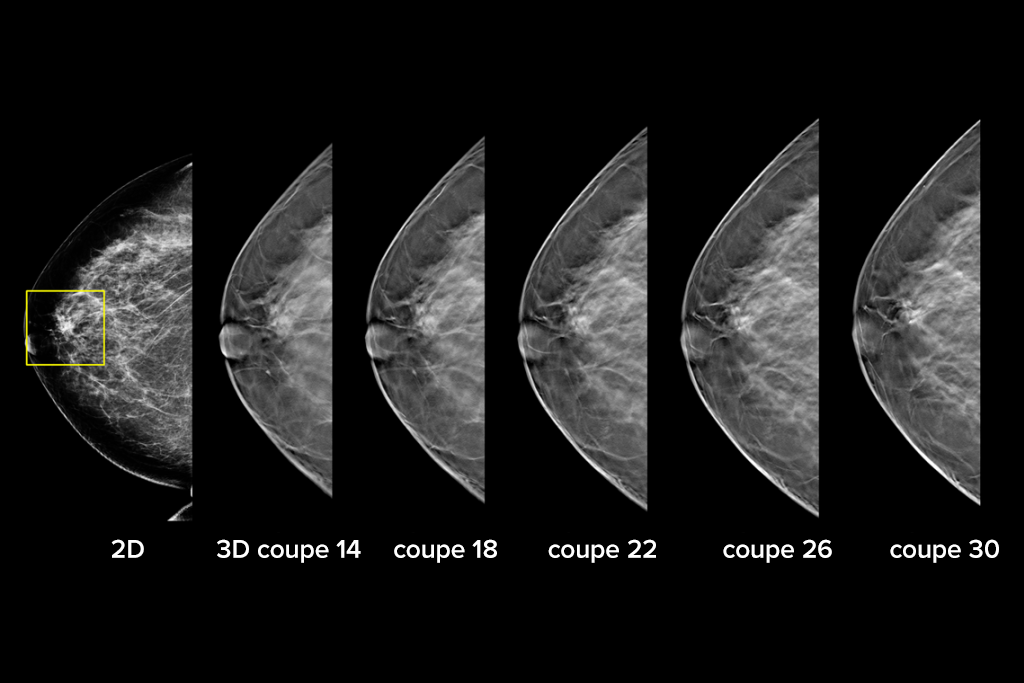

Images cliniques

Images cliniques d’une mammographie

Images cliniques d’une mammographie avec lésion suspecte

• un jeu d'images 2D et 3D, où l'image 2D peut être soit une image MNPC soit une image 2D générée à partir du jeu d'images 3D, et où le jeu d'images 3D peut être visualisé soit en coupes 3D de 1 mm soit en SmartSlices 3D de 6 mm.